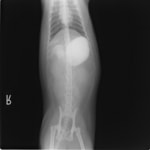

嘔吐が改善しないため、消化管バリウム造影検査を実施。

以下、

消化管バリウム造影レントゲン

バリウム造影3時間経過するも、胃内からバリウム排泄なく同日内視鏡検査を実施。

内視鏡検査結果:内視鏡下にて、バスケット鉗子を用いて摘出。

症例は、机の上に置いていたピスタチオのお菓子を誤飲していました。その後の経過は良好です。本症例は、内視鏡下にて摘出ができましたが、球状・立体などの大きな異物は、腸の途中で詰まりやすく、内視鏡下での摘出が困難な場合もあります。その際は、開腹下にて腸内の異物を摘出しなくてはなりません。動物たちは、思わぬ物を誤飲することがあります。お留守番時・就寝時は、誤飲をしやすい時間帯ですので注意しましょう。